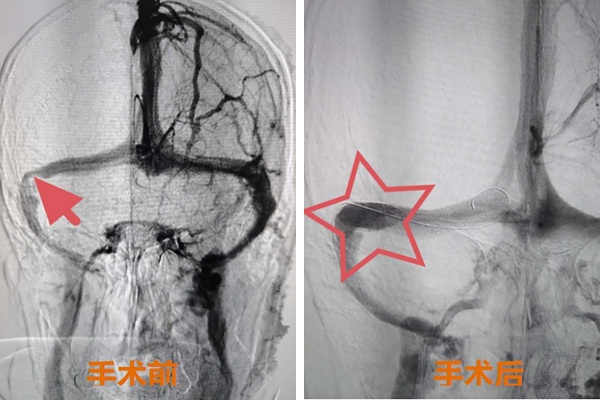

为明确血管狭窄程度及压力梯度,神经医学中心张志勇主任团队与患者及家属进行充分沟通后,于2025年8月13日在局麻下为郭奶奶实施全脑血管造影术。造影结果显示,患者右侧横窦及乙状窦交界处狭窄率约70%(图 1),微导管静脉窦压力测定显示狭窄远端与近端压力差达8mmHg,具备明确手术指征。在全面评估病情并做好周密术前准备后,张志勇主任带领介入团队果断决策,同期为患者实施全麻下颅内静脉窦球囊扩张及支架植入术。手术过程精准顺利,术后造影显示狭窄完全解除(图 2),再次测压已无明显压力梯度。